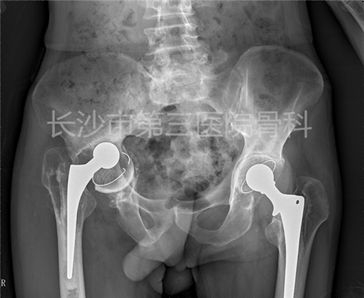

二期翻修术前X片

近期我院收治一例髋关节置换感染的男性患者,65岁,因双髋置换术后5年,右大腿疼痛、活动受限1年入院。

5年前因“双侧股骨头缺血性坏死”在当地医院行“左、右侧人工全髋关节置换术”(2009.03、2009.9)。

2013年12月患者无明显诱因出现右大腿疼痛,右下肢跛行,疼痛逐渐加重,2014年10月就诊于某市骨科医院,行右大腿穿刺抽液细菌培养+药敏示:金黄色葡萄球菌感染,予抗感染治疗无缓解,1周前出现发热,体温最高达38.5℃。术前Harris评分:28。

PE:右大腿中上段肿胀,皮肤略红,皮温高,质硬,压痛(+),右下肢纵向叩击痛(+),右髋屈45°~伸0°,右髋内收、外展部分受限。伤口后外侧见长约15cm的术后疤痕。

入院后BR(2014-10-9):WBC:9.06×109/L,N 75%, Hb 83g/L。D-二聚体:3.5ug/L,ESR 67mm/h, CRP 39.7ng/L,降钙素原(PCT):0.2 ng/ml。